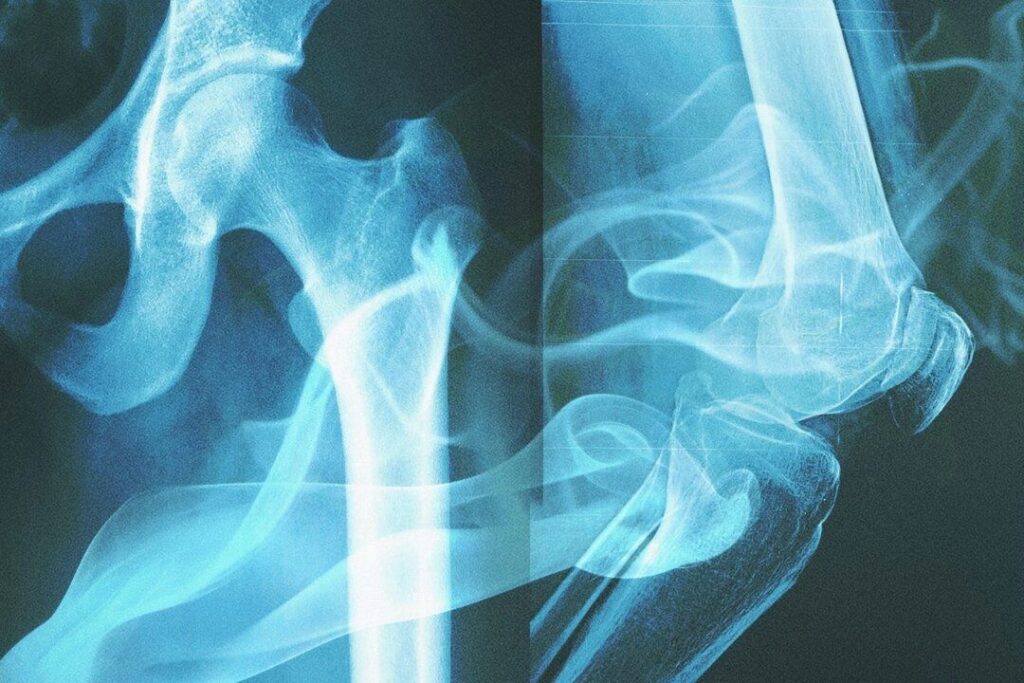

研究チームは各個体の大腿骨(太ももの骨)から、お米一粒ほどの重さである約40mgの皮質骨を抽出し、液体クロマトグラフィー高分解能質量分析法で検査しました。この技術は、サンプル内の化学物質を質量や構造で分離し、正確に特定することができます。

研究では、骨組織の中でも特に緻密な外層である皮質骨に注目しており、これは外部環境の影響を受けにくい特徴があります。たとえ土壌の成分や湿度によって骨の表面の色が変わっても、内部にある化学シグネチャーは保たれます。